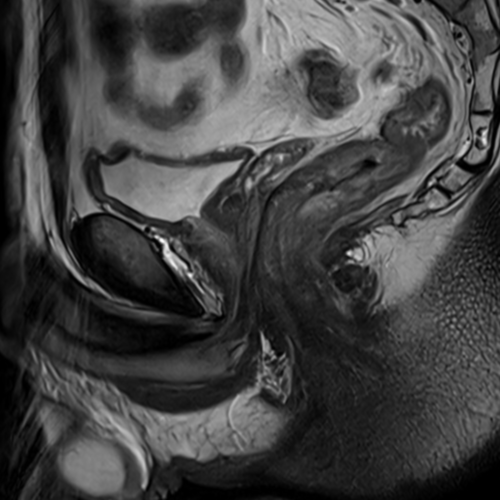

Cet examen est réalisé pour analyser les différentes structures anatomiques du canal anal;

Le canal anal est le segment terminal du tube digestif, faisant suite au rectum. Il mesure 3 à 4 cm.

Cette IRM est réalisée en cas de douleurs, de masse anale, de suspicion de cancer, de fistule.

Quels sont les résultats possibles d’une IRM du canal anal ?

Cette examen permets de diagnostiquer:

- Les tumeurs .

- Les fistules .

- Les abcès de la marge anale.